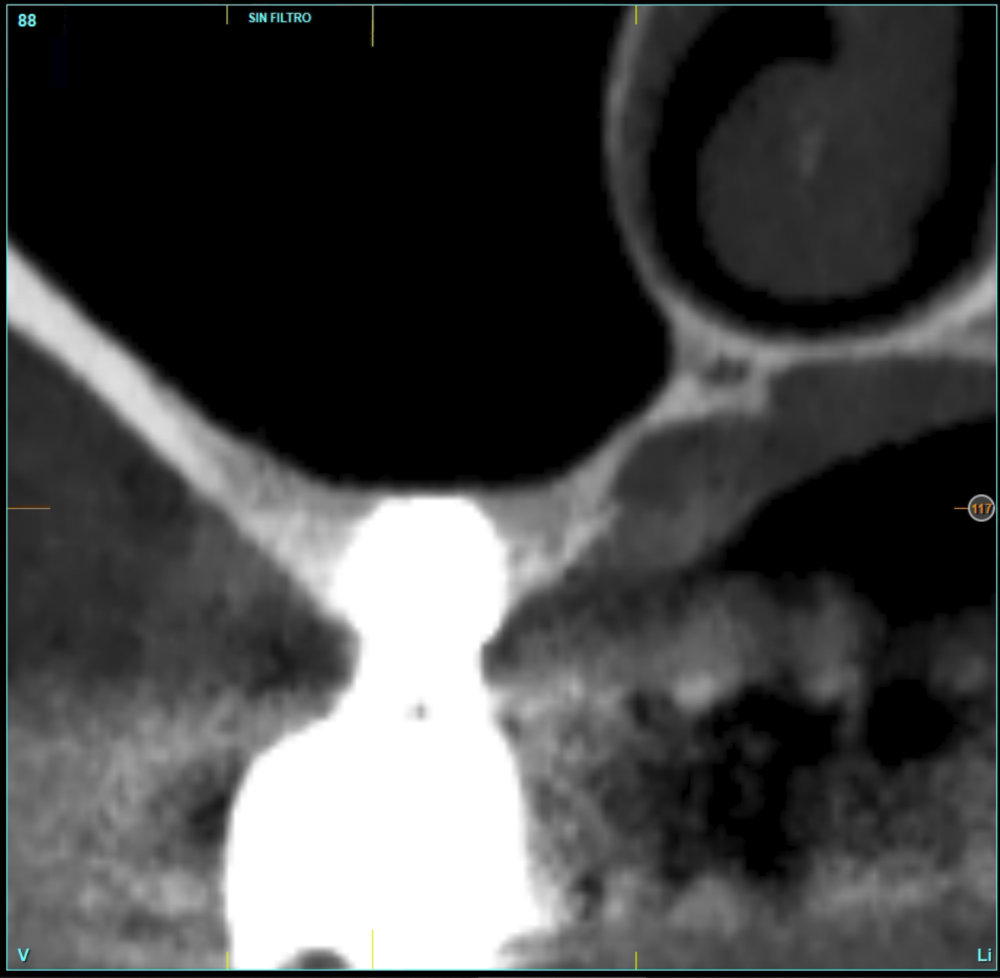

In all cases, a diagnosis was made based on study models, intraoral examination of the patient and performing a Cone-beam analysed using the specific BTI-Scan 3 software (Biotechnology Institute, Vitoria, Alava, Spain).

Patients attend subsequent check-ups performing a control Cone-Beam after 5 months (before loading the implant) and after one year of the load, performing a new measurement in these images to analyse the bone gain and the maintenance of the same. In these check-ups, data are collected on prosthetic complications or crestal bone loss in these patients, as well as possible failures.

The mean height of the residual bone volume was 3.1 mm (+/- 0.3 mm with a range of 3-4 mm). In all cases, transcrestal sinus elevation was performed, with particulate autologous bone obtained from milling the neo alveolus generation zone for implant insertion, being the average of this elevation above the apex of the implant of 2.8 mm (+/- 0.99 range 1.9 -5 mm). In the CT control scan after one year of inserting the studied implants, the bone gain achieved was maintained, no decrease in the volume gained was observed, only three cases showed a decrease of between 0.4 and 0.5 mm of the initial volume at the end (Table).

Figures 2-19 show one of the cases included in the study.